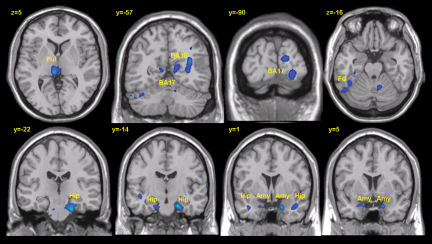

In early stages of intentional forgetting, part of the brain’s prefrontal cortex dampens activity in neural areas involved in visual and other sensory aspects of memory, Depue and his colleagues report in the July 13 Science. As the process of forgetting continues, a different prefrontal area quells the activity of structures implicated in conscious recall of information and emotions such as fear.

Brain images indicated that blood flow, a marker of neural activity, increased in a specific prefrontal area early during volunteers’ attempts at forgetting. At the same time, blood flow declined in the visual cortex and the thalamus, areas that handle sensory components of memory. The prefrontal cortex regulates these and other structures through networks of anatomical connections.

A different neural pattern eventually appeared among memory suppressors. Pronounced activity in another prefrontal area accompanied sparse blood flow in the hippocampus and amygdala, areas responsible for consciously recalled memories and fear conditioning, respectively.